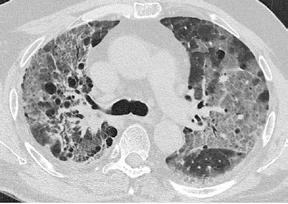

El día 18/2/2022 el paciente refiere dolor torácico. Se realiza un electrocardiograma, que muestra elevación del segmento ST en las derivaciones anteriores en relación con un infarto agudo de miocardio (IAM) anterior. Se activa código infarto y se realiza una coronariografía emergente, que muestra una oclusión de perfil embólico en la arteria descendente anterior media (Figura 1, flecha amarilla). Se trata con trombectomía aspirativa con buen resultado angiográfico final con flujo TIMI 3. Se inicia tratamiento con perfusión de heparina sódica. El día 19/2 el paciente comienza con cefalea muy intensa y afasia, por lo que se activa nuevamente código ictus y se realiza un angioTAC craneal que muestra una hemorragia subaracnoidea (HSA) de predominio izquierdo secundaria a sangrado por un aneurisma disecante de la rama M2 de la arteria cerebral media izquierda (Figura 2, flecha amarilla). Se decide completar estudio con una angiografía que confirma los hallazgos del TAC. Por el alto riesgo de resangrado y la necesidad de anticoagulación oral permanente, se decide embolización del aneurisma con coils, que resulta exitoso (Figura 3, flecha amarilla). Se reinicia durante el ingreso perfusión de heparina sódica y unos días antes del alta se comienza con anticoagulación oral con apixaban 5 mg/12 horas. La evolución clínica es favorable, siendo la exploración física al alta normal. Tras tres años de seguimiento bajo tratamiento con apixaban 5 mg/12 horas no han sido reportados nuevos episodios de sangrado ni de trombosis.

Figuras 1 y 2: Prótesis aórtica migrada y disección aórtica focal tipo A, de origen en la curvatura menor del arco aórtico (zona 0) hasta la bifurcación de la arteria braquiocefálica derecha; sin afectación de del resto de troncos supra-aórticos, del resto del cayado aórtico o de la aorta descendente.